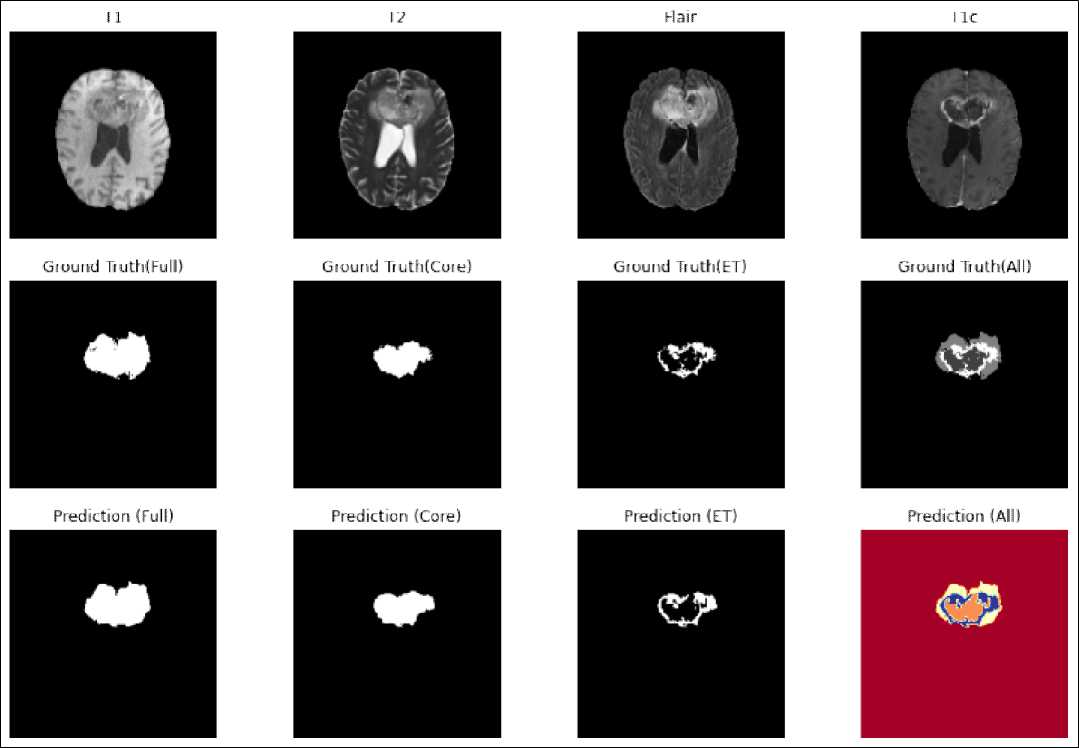

Matrik evaluasi dibagi menjadi tiga wilayah tumor yang bernama a) Complete/Full Tumor (necrosis, edama, enhancing dan non enhancing tumor), wilayah kedua adalah Core Tumor (sama seperti Complete Tumor tanpa edama) dan yang terakhir adalah Enhancing Tumor.

dihasilkan dengan menggunakan fungsi model.evaluate() Berdasarkan Tabel I, proses segmentasi Full Tumor sehingga mengetahui rata-rata akurasi dan loss yang dihasilkan. memperoleh hasil akurasi yang paling tinggi dibandingkan dengan yang lainnya dikarenakan area tumornya paling besar dan paling jelas dibandingkan dengan area tumor lainnya. Gambar 11 menunjukkan hasil prediksi segmentasi tumor otak yang dibandingkan dengan segmentasi manual dari dokter. Dapat dilihat bahwa hasil segmentasi otomatis memberikan kemiripan yang tinggi dengan segmentasi manual.

Gambar 11 Hasil Prediksi Dari Model U-NET Dengan Fungsi Aktivasi ReLU

Berdasarkan pengujian yang dilakukan dan hasil yang ditunjukkan pada Tabel I, nilai akurasi pada saat validasi [2] untuk full tumor, core tumor dan enhancing tumor berturut-turut adalah sebagai berikut: 90.22%, 78.09%, 80.20%. [3]